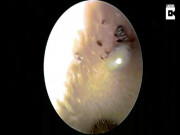

Những con ong được tìm thấy trong mắt người phụ nữ.

Theo Daily mail, các bác sĩ tại bệnh viện Đại học Fooyin ở Đài Loan đã tìm thấy côn trùng trong mắt người phụ nữ.

Bác sĩ Hung Chi-ting, trưởng khoa nhãn khoa, nói đây là lần đầu tiên họ gặp trường hợp như vậy.

Bác sĩ Hung nói trong cuộc họp báo rằng cô He bị viêm mô tế bào và viêm giác mạc. Đây là kết quả của việc bị ong mồ hôi uống nước mắt trong mắt cô gái suốt nhiều giờ.

Bác sĩ kiểm tra mắt của cô He.

Bác sĩ Hung nói: “Tôi lấy ra được 4 con ong mồ hôi còn sống nguyên. Loài ong này rất thích vị mặn tiết ra từ mồ hôi con người.